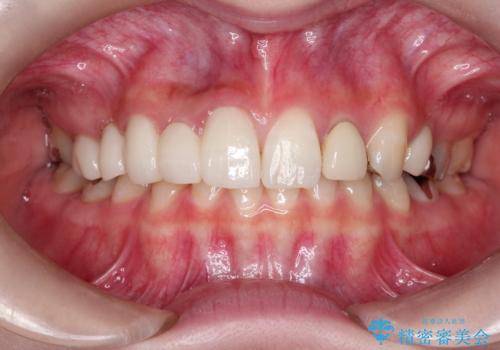

かぶせものと歯ぐきの境目が黒い 40代女性

保険のかぶせ物・詰め物を金属を使わないセラミックへ 自然な見た目へ